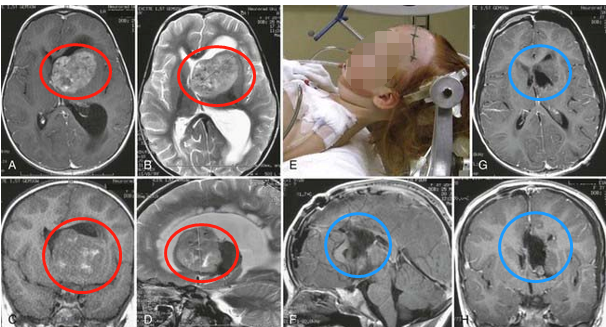

INC國際神經(jīng)外科醫(yī)生集團巴特朗菲教授案例(下圖),術(shù)前軸位(A和B)、冠狀位(C)和矢狀位(D)MR的3歲女孩意識障礙。較初,外腦室引流放置治療閉塞性腦積水。E、術(shù)中神經(jīng)導(dǎo)航輔助下仰臥位手術(shù)。F-H、術(shù)后MR顯示間變性室管膜瘤完全切除。術(shù)后平安無事,預(yù)后良好。